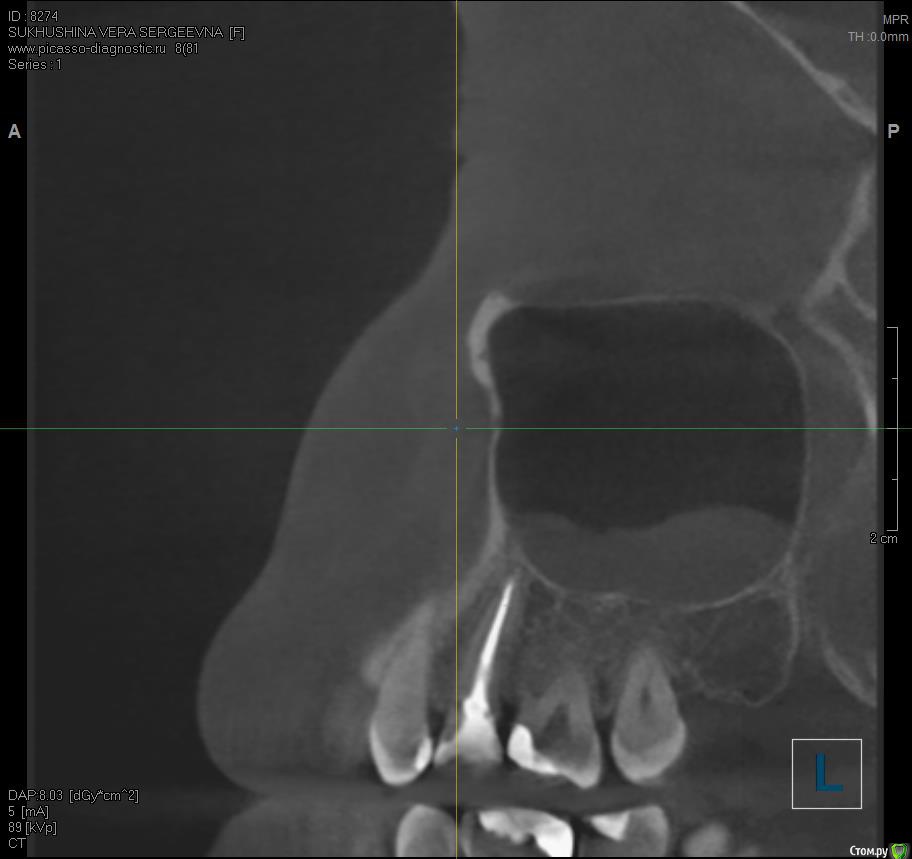

Verasss Опубликовано 8 октября, 2016 Автор Поделиться Опубликовано 8 октября, 2016 КТ от 08.09. Извините, что в таком виде, надо менять ОЗУ. Ссылка на комментарий

Verasss Опубликовано 28 октября, 2016 Автор Поделиться Опубликовано 28 октября, 2016 Добрый вечер! Ещё раз попытаюсь прикрепить скриншоты КТ от сентября. Если качество совсем не устраивает, подскажите, пожалуйста, какие сделать снимки?К сожалению, программа не позволяет вывести снимки на полный экран и заскриншотить в более хорошем качестве. Ссылка на комментарий

Verasss Опубликовано 28 октября, 2016 Автор Поделиться Опубликовано 28 октября, 2016 еще снимки Ссылка на комментарий

Verasss Опубликовано 28 октября, 2016 Автор Поделиться Опубликовано 28 октября, 2016 и еще Ссылка на комментарий

DmitrySH Опубликовано 8 октября, 2016 Поделиться Опубликовано 8 октября, 2016 В таком виде КТ малоинформативно. Но гайморита нет. Ссылка на комментарий

Verasss Опубликовано 23 ноября, 2016 Автор Поделиться Опубликовано 23 ноября, 2016 Сделала ещё 1 кт, спустя почти 2,5 месяца после первого. Посмотрите, пожалуйста, есть ли изменения? Напомню, что пункцию гайморовой мне сделали. Ссылка на комментарий